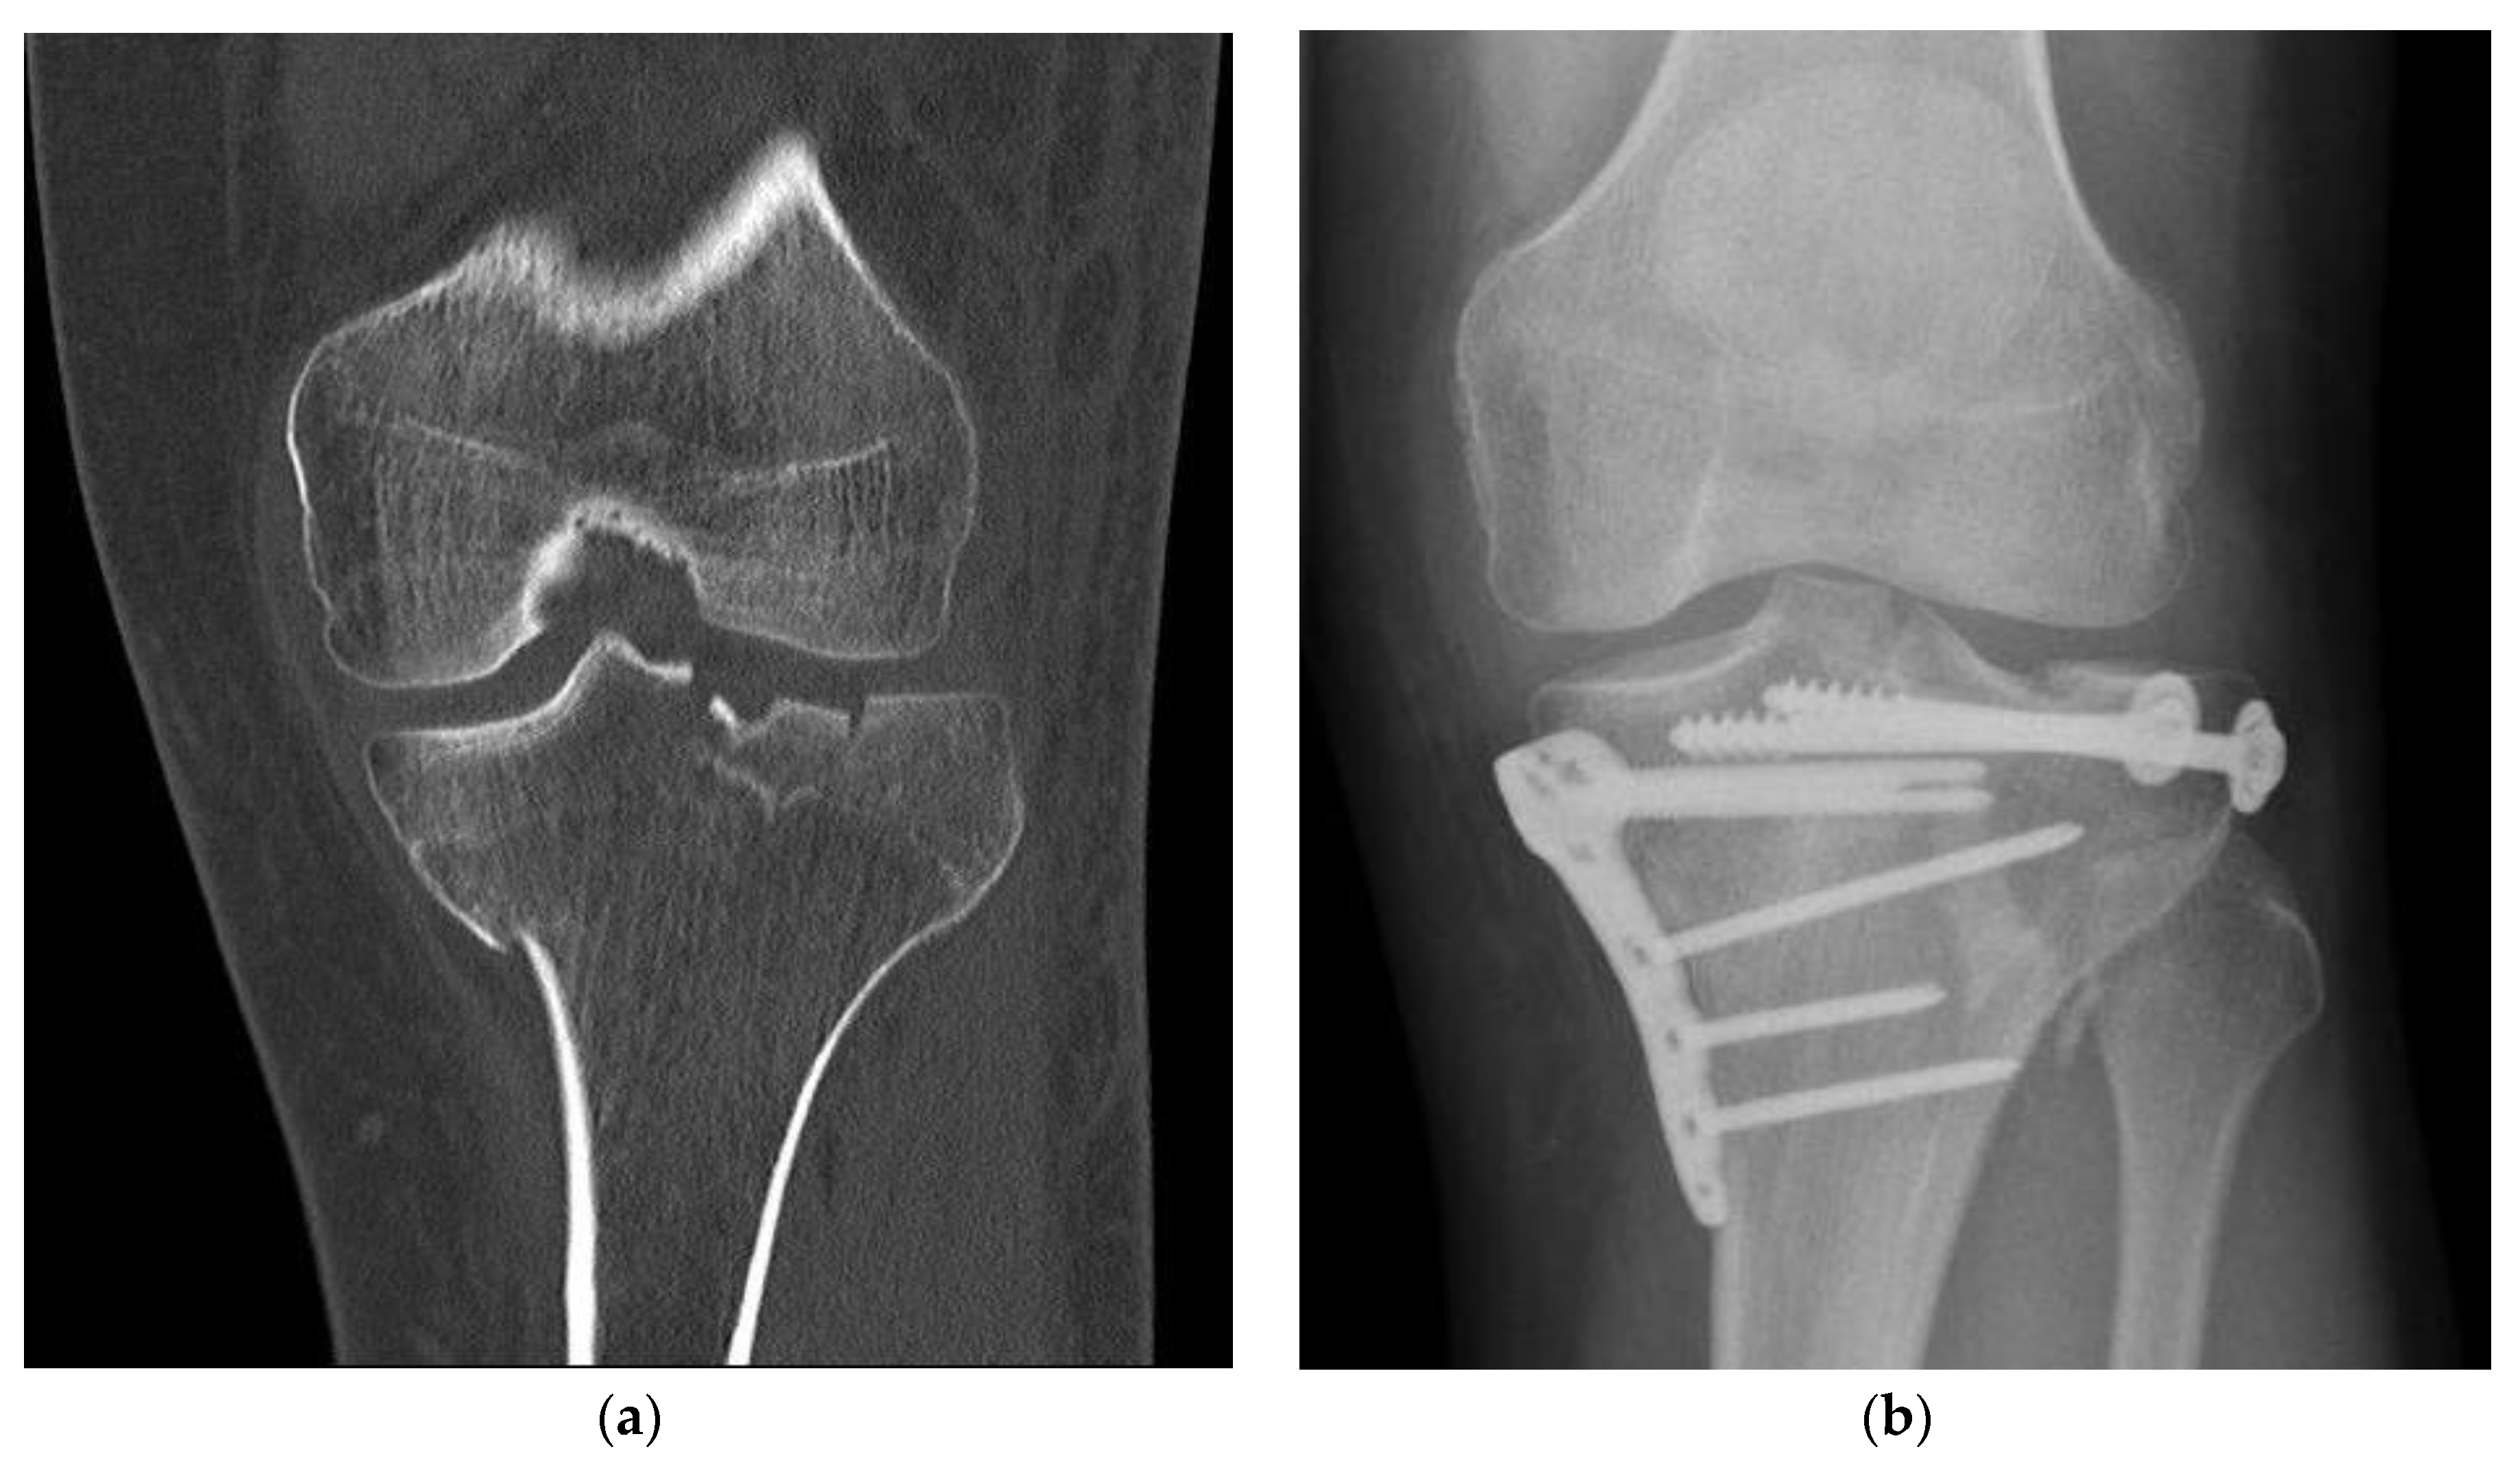

Figure 2. Fracture treatment of a proximal tibial fracture by surgical bone substitute material augmentation: (a) Preoperative CT scan demonstrates a metaphyseal compression fracture with intra- and extraarticular fracture gaps; (b) Alloplastic bone material substitute augmentation replaces the bone material of the fracture vault defects.